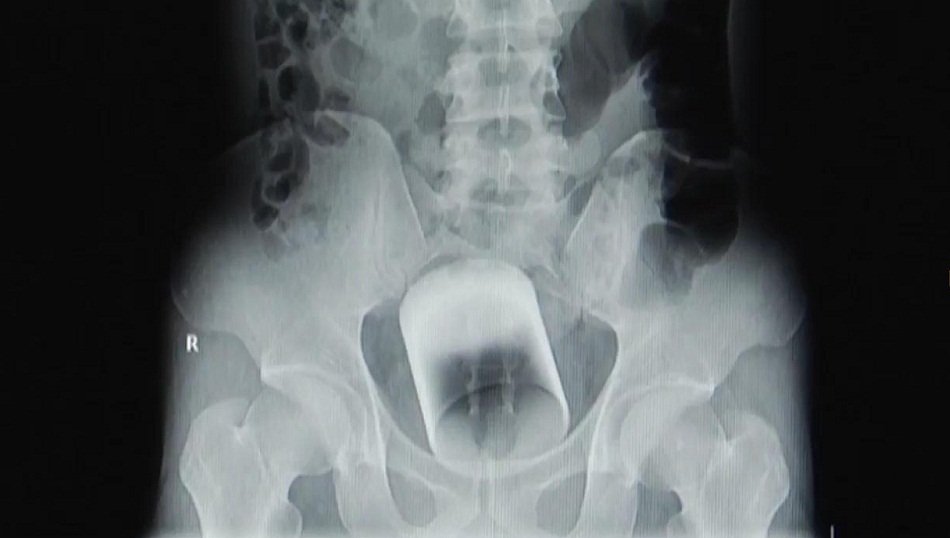

07/09/2017 07:22:00 +07:00Ảnh chụp X-quang cho thấy chiếc cốc thủy tinh có đường kính 7cm, cao 8cm, nằm ở phần trên trực tràng và có thể khiến người đàn ông mất mạng nếu không được lấy ra kịp thời.